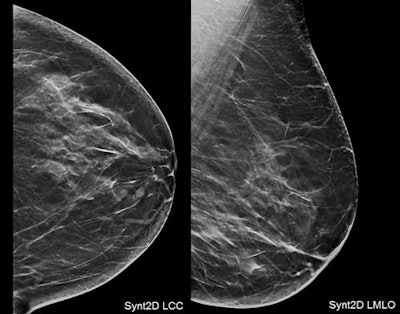

Using digital breast tomosynthesis (DBT) with synthesized 2D mammography increases cancer detection and reduces recall rates when compared with standard digital mammography alone, based on interim clinical trial results from Italy.

The study compared women screened using standard full-field digital mammography (FFDM) with women screened using DBT plus synthesized 2D mammography, which is a mammogram reconstructed from DBT data. The research team, led by Dr. Daniela Bernardi from the radiology department at U.O. Senologia Clinica & Screening Mammografico in Trento, found synthesized 2D mammography plus DBT increased the cancer detection rate by nearly four cancers per 1,000 screens and reduced the recall rate by 0.66%.